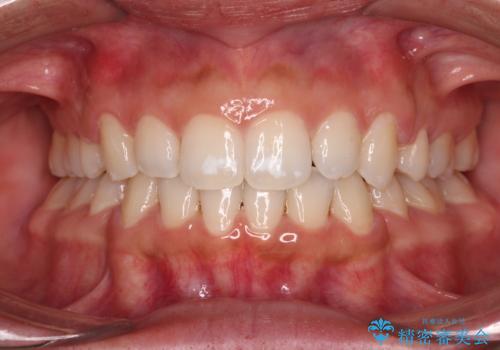

2年から2年半の治療期間を想定しており、予定通りの期間で無事に終了することができました。

唇や顎先に力を入れないなくてもスムーズに唇を閉じることができるようになりました。